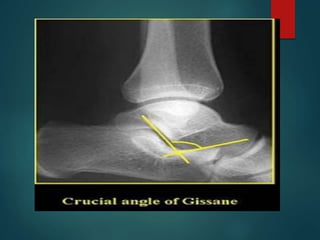

The critical angle of Gissane

 It is formed by a line along the lateral margin of the

posterior facet and another line extending anterior to

the beak of the calcaneus. The normal value is 95 to 105

degrees with an increase representing posterior facet

collapse